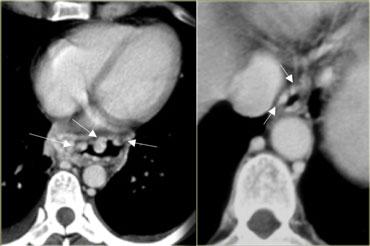

Bên trái là hình ảnh một bệnh nhân bị tụ máu thực quản.

Bệnh nhân nhập viện với triệu chứng đau ngực và khó nuốt sau khi nôn mửa.

Ngoài hình ảnh động mạch chủ ngoằn ngoèo, X-quang ngực bình thường.

Chụp thực quản barium cho thấy lòng thực quản hẹp (các mũi tên) trên phim thẳng và lòng thực quản dẹt trên phim nghiêng (các đầu mũi tên), gợi ý tụ máu trong thành thực quản.

Trên CT, chẩn đoán tụ máu trong thành thực quản được xác nhận.

Khối tụ máu thành thực quản tăng tỷ trọng (đầu mũi tên) được thấy cạnh ống thông mũi – dạ dày (mũi tên).

Sau điều trị bảo tồn, sáu tháng sau chụp thực quản barium cho kết quả bình thường.